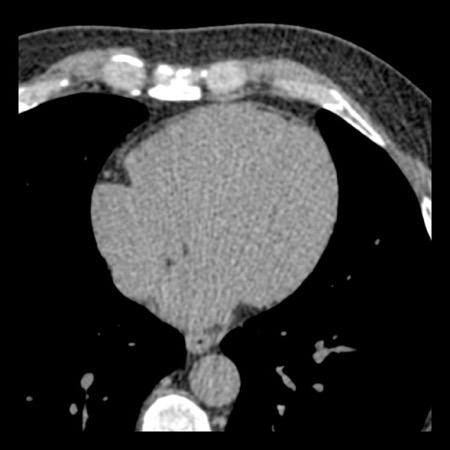

case 4 – CAD-RADS 3/P1/I+ thrombus left ventricle

First, scroll through the CTA images.

How would you describe the findings on the coronary CTA?

The findings are:

- Moderate (50-69%)

stenosis in the proximal LAD caused by a non-calcified plaque. - Variant of

sinoatrial (SA) nodal artery. The artery usually arises from the RCA as a second

branch after the conus artery, however in this case it arises from the LCX,

courses behind the aorta, anastomosing with the right atrium and with a small

branch supplies the SA-node of the heart. - Thrombus in the

apex of the left ventricle. - CTP was performed

in this patient. CTP showed a perfusion defect at stress imaging in the

territory of the LAD (I+), at rest no perfusion defect was visible.

This patient classifies as CAD-RADS 3/P1/I+, which means

this patient requires further investigation.